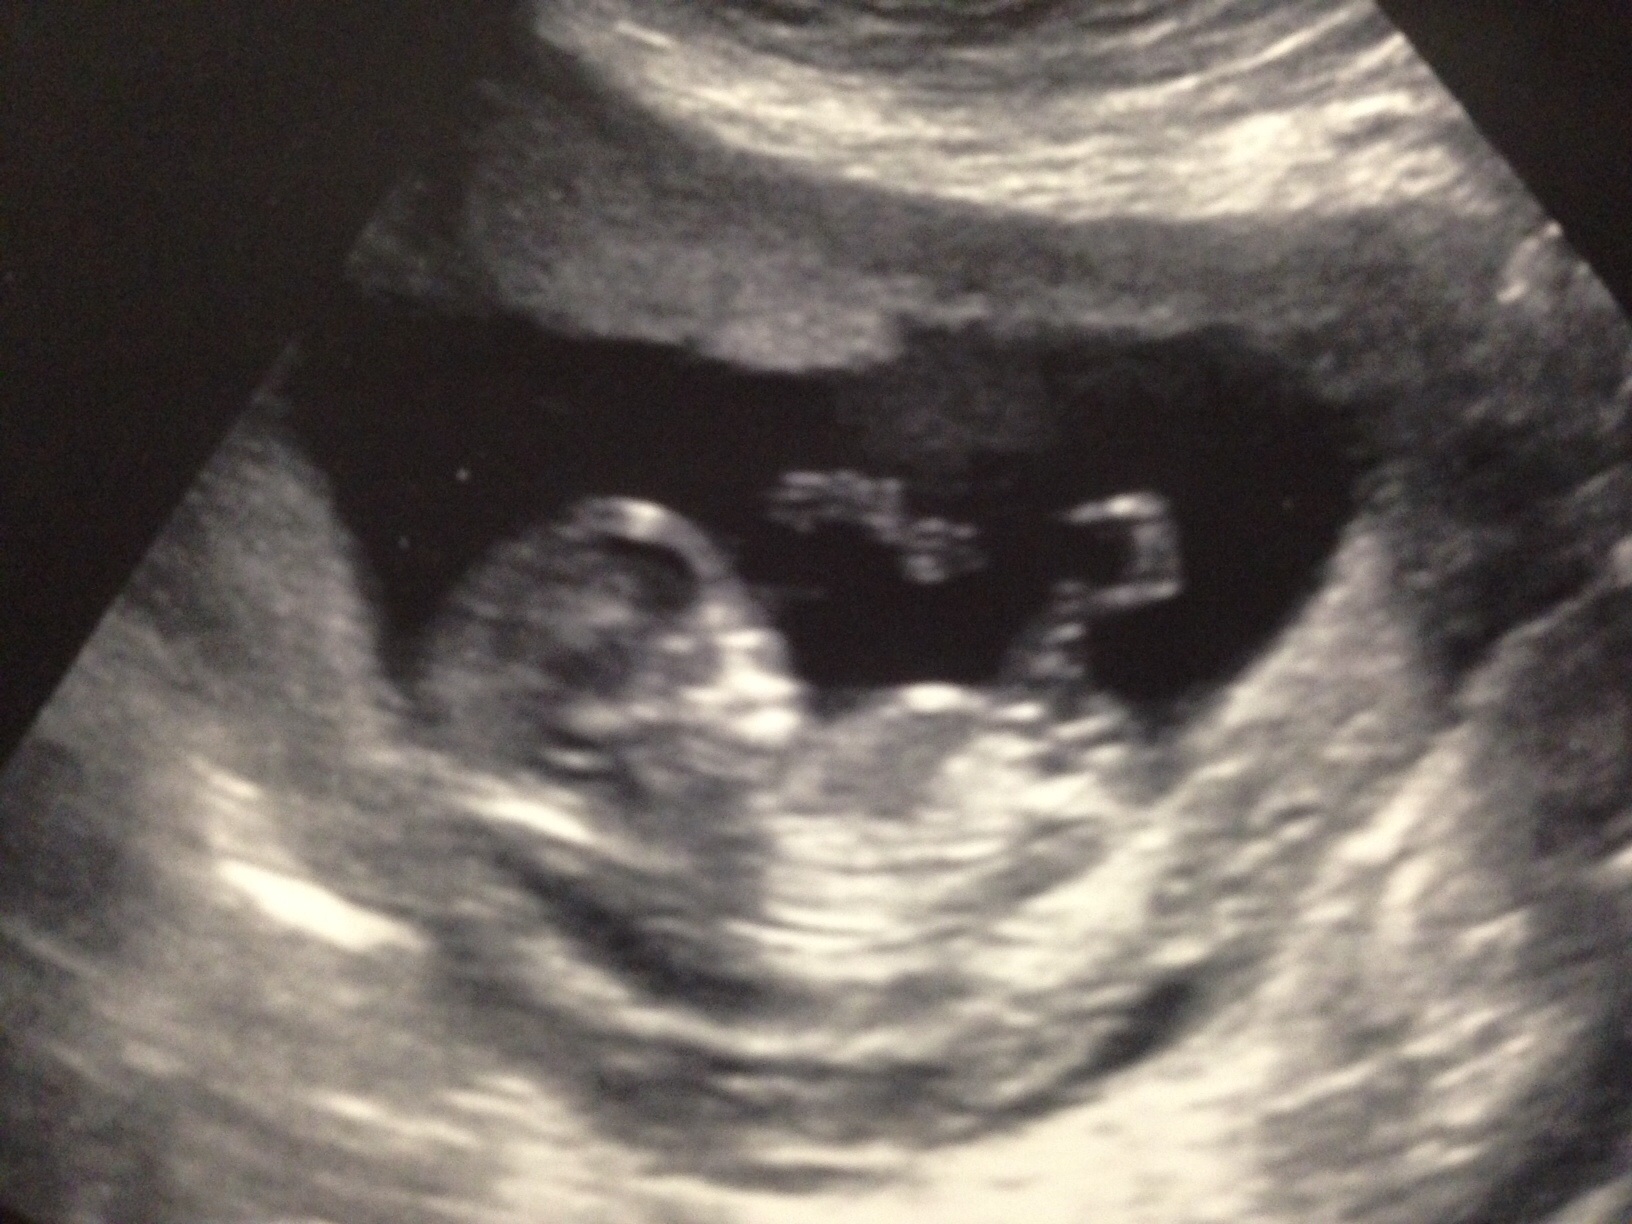

11 wks 6 days....nub guesses?

I know it's early, but I thought I'd try anyway! I find this a lot of fun (guessing others' genders too) so I thought I'd join the action...any guesses are fun and very much appreciated.

Attachment 18080Attachment 18081..11 weeks 6 days.

Had my 20 week anatomy scan today and it's a :DD: GIRL! I never, ever thought I'd be saying that. Thank you, thank you, thank you GD, Atomic and all you ladies for your advice and words of wisdom in swaying. I will post my sway soon :)